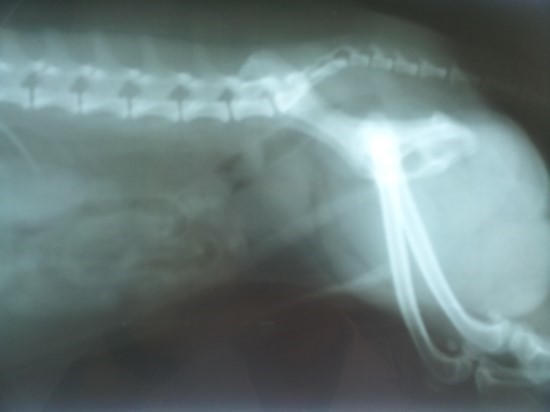

8. 골반통

골반 고통은 진행성 전립선암의 징후일 수 있어요. 고통은 일반적으로 옆구리, 배, 골반 부위에서 느껴지지만 암이 진행됨에 따라 뼈에서도 고통이 느껴질 수 있어요. 이런 부위에 고통이 있고 요로 감염 증상이 나타나면 의사를 내원해서 정확한 진단을 받는 것이 좋아요.